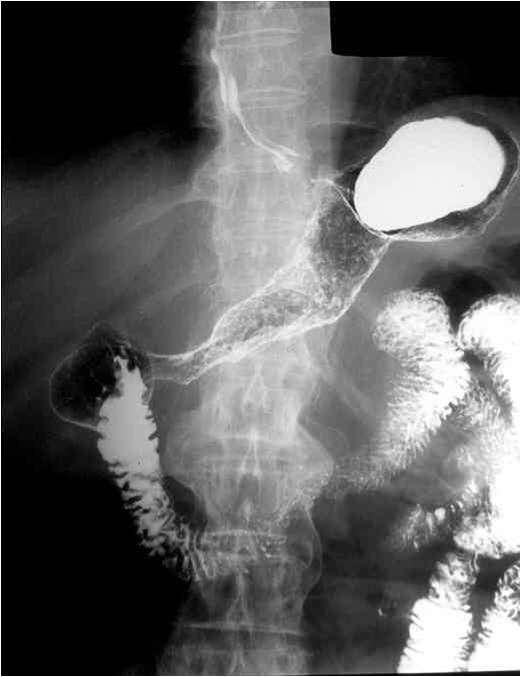

Double-contrast irrigoscopy.

Fig.23.: Radiographic image: multiple, round filling defects are seen on the sigma and on the descending colon.

Image

Fig.24.: Double-contrast irrigoscopy